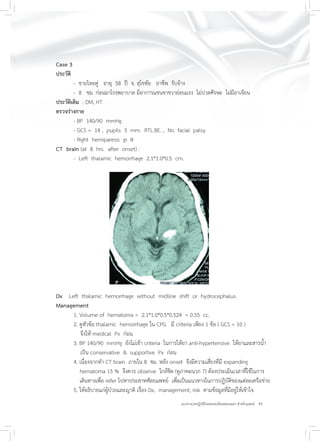

Case 3

ประวัติ

- ชายไทยคู่ อายุ 58 ปี จ. สุโขทัย อาชีพ รับจ้าง

- 8 ชม. ก่อนมาโรงพยาบาล มีอาการแขนขาขวาอ่อนแรง ไม่ปวดศีรษะ ไม่มีอาเจียน

ประวัติเดิม : DM, HT

ตรวจร่างกาย

- BP 140/90 mmHg.

- GCS = 14 , pupils 3 mm. RTL.BE. , No facial palsy

- Right hemiparesis gr. III

CT brain (at 8 hrs. after onset) :

- Left thalamic hemorrhage 2.1*1.0*0.5 cm.

Dx Left thalamic hemorrhage without midline shift or hydrocephalus.

Management

1. Volume of hematoma = 2.1*1.0*0.5*0.524 = 0.55 cc.

2. ดูหัวข้อ thalamic hemorrhage ใน CPG มี criteria เพียง 1 ข้อ ( GCS = 10 )

จึงให้ medical Px ก่อน

3. BP 140/90 mmHg ยังไม่เข้า criteria ในการให้ยา anti-hypertensive ให้ยาและสารน้ำ

เป็น conservative & supportive Px ก่อน

4. เนื่องจากทำ CT brain ภายใน 8 ชม. หลัง onset จึงมีความเสี่ยงที่มี expanding

hematoma 15 % จึงควร observe ใกล้ชิด (ดูภาคผนวก 7) ต้องประเมินเวลาที่ใช้ในการ

เดินทางเพื่อ refer ไปหาประสาทศัลยแพทย์ เพื่อเป็นแนวทางในการปฏิบัติของแต่ละเครือข่าย

5. ให้อธิบายแก่ผู้ป่วยและญาติ เรื่อง Dx, management, risk ตามข้อมูลที่มีอยู่ให้เข้าใจ